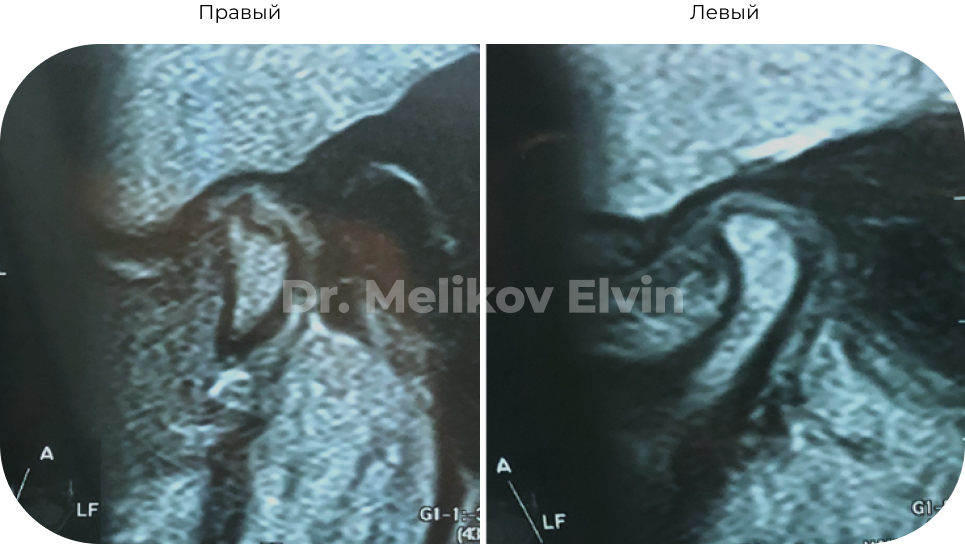

Компьютерная томография ДО.